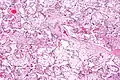

| Micrograph of villous immaturity. H&E stain. | |

Immature chorionic villi are larger and have more central blood vessels; thus, the diffusion distance for gas and nutrient exchange is larger and, therefore, placental function is impaired.

High mag.